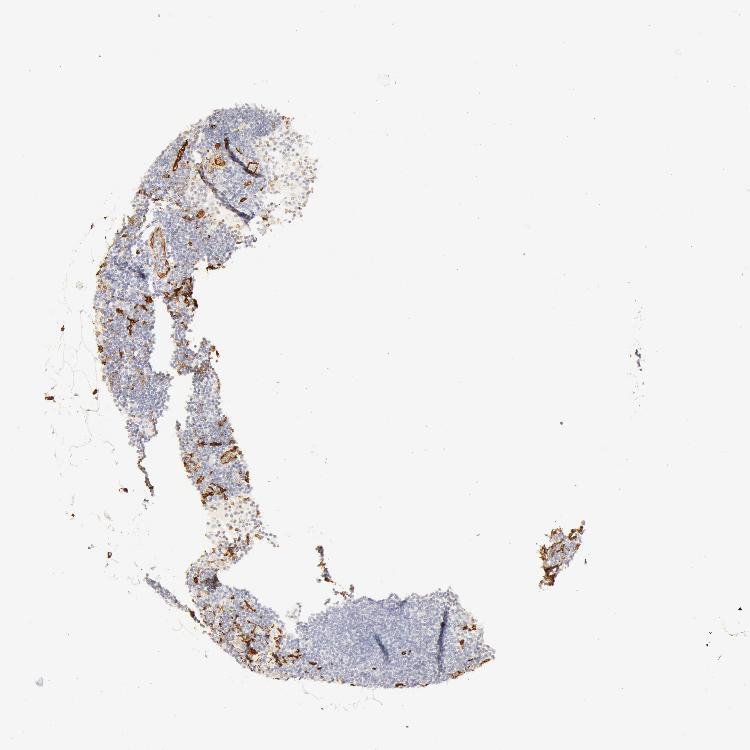

TISSUE PRIMARY DATA LYMPH NODE Show tissue menu

Lymph node

LYMPH NODE - Antibody stainingi

Antibody staining in the annotated cell types in the current human tissue is reported as not detected, low, medium, or high, based on conventional immunohistochemistry profiling in selected tissues. This score is based on the combination of the staining intensity and fraction of stained cells.

Each image is clickable and will lead to virtual microscopy that enables deeper exploration of all samples and also displays staining intensity scores, fraction scores and subcellular localization as well as patient and tissue information for each sample.

Antibody HPA019206Antibody CAB001707

Germinal center cells Not detectedNot detected

Non-germinal center cells Not detectedNot detected